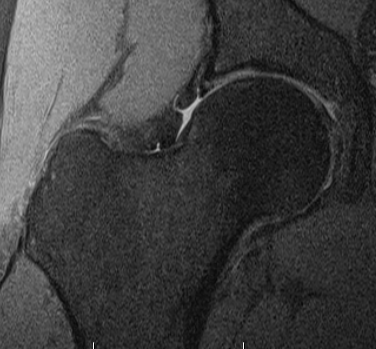

MRI

Labral tears

Best seen on coronal MRI